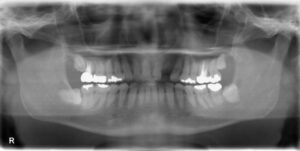

• 上顎大臼歯2本欠損症例

BEFORE AFTER 50歳女性/上2本欠損/インプラント埋込手術 【治療内容】 左上第一大臼歯、第二大臼歯は他院で…